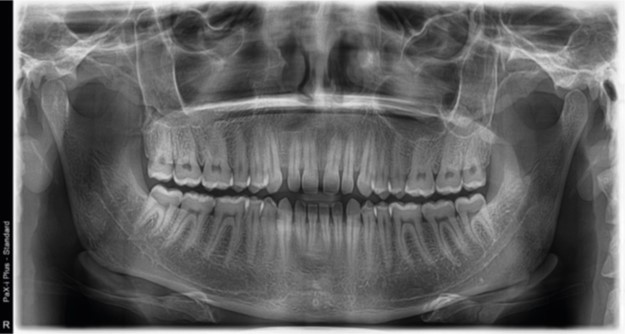

PaX-i Plus provides the most precise and high quality panoramic image by innovative imaging process and accumulated experience in dental imaging from VATECH. It improves your diagnostic accuracy with increased treatment planning and patient satisfaction.